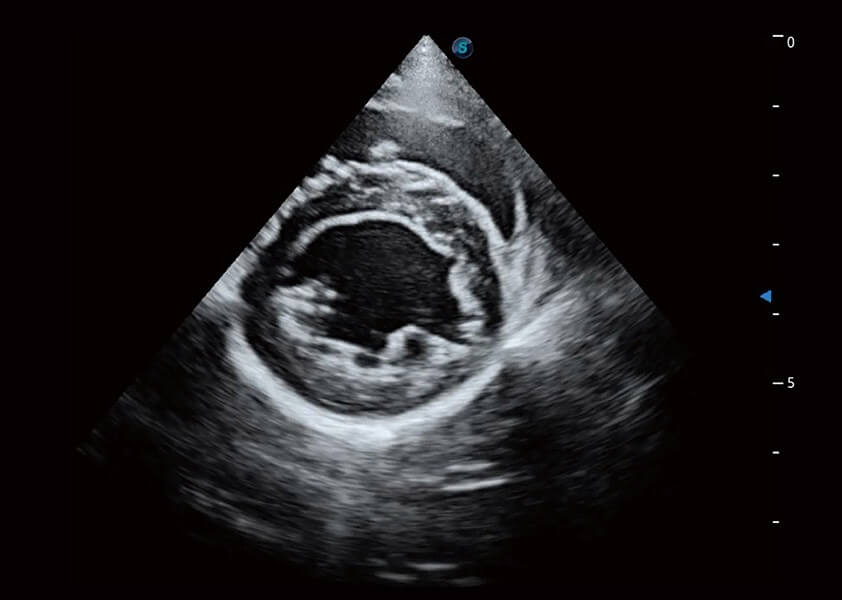

ProPet 60 作为一款高端台式动物超声设备,为动物医生的日常诊断提供了一系列贴合动物临床需求、解决临床实际问题的高级成像功能。凭借全系列高清探头,满足医生对腹部、心脏、生殖、浅表、肌骨等成像的所有需求,切实帮助您提升检查效率,提高诊断信心。

兽用彩色多普勒超声诊断系统

动物是人类最亲密的朋友和最值得信赖的伙伴。DB中国旗舰官方网站也一直致力于探索动物专用的超声影像解决方案。 全新推出的ProPet系列,是DB中国旗舰官方网站在动物超声影像智能化、专业化、精准化的一次跨越式革新。动物不能用言语来表述自己的不适,通过超声影像,ProPet系列搭建了动物医生与不同物种沟通的“桥梁”,为动物医生注入了“治愈之力”。